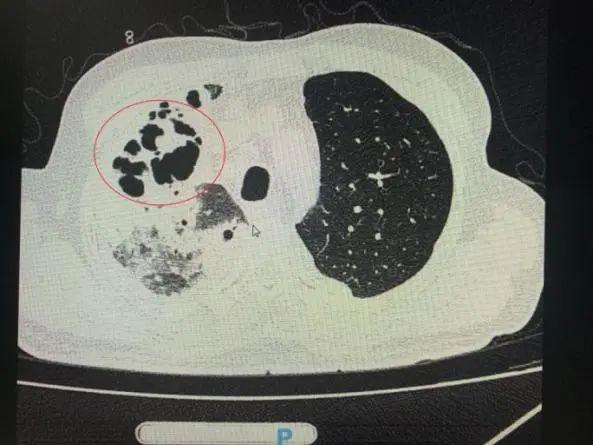

番禺院區(qū)呼吸內(nèi)科何夢(mèng)璋主任接診后,對(duì)鐘叔進(jìn)行詳細(xì)檢查。此時(shí),鐘叔的病情已經(jīng)十分危急,由于不能自主呼吸,他帶上了呼吸機(jī)輔助呼吸調(diào)節(jié)??吹界娛逍仄瑫r(shí),醫(yī)護(hù)人員頭皮也一陣發(fā)麻,胸部CT可見(jiàn)雙肺多發(fā)的炎癥浸潤(rùn)、雙肺多發(fā)空洞。通俗來(lái)說(shuō),鐘叔的肺部已經(jīng)被病原體蠶食,啃出個(gè)大小各異的洞!可怕的是,這種病變對(duì)肺功能的破壞是性、不可恢復(fù)的。根據(jù)鐘叔病史以及胸部CT結(jié)果,終診斷為“吸入性肺膿腫”。

鐘叔的肺部被病原體蠶食,啃出個(gè)大小各異的洞。